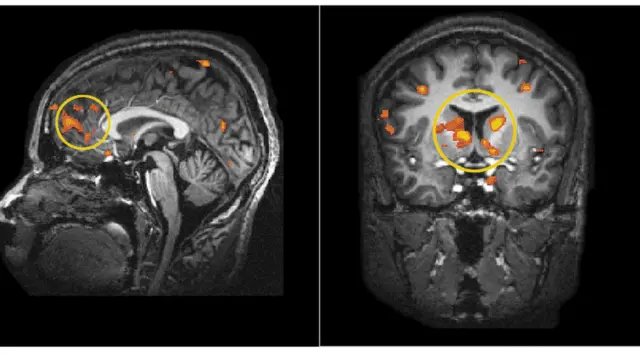

మెదడులోని కణాలు, నాడీవ్యవస్థ మధ్య ఉండే క్లిష్టమైన, సున్నితమైన సంబంధాలను మనకు అనుగుణంగా మలచుకుంటూ సామర్థ్యాలను, జ్ఞానాన్ని పెంచుకుంటుంటాం. ఇదంతా సాధనతోనే జరుగుతుంది. మనలోని ప్రతికూల భావనలను తొలగిస్తూ ఆత్మవిశ్వాసాన్ని పెంపొందించేందుకు న్యూరోసైన్స్ కూడా ఉపయోగపడుతుంది. మెదడులోని కీలక ప్రాంతాలను మనకు కావాల్సిన పనిలో నిమగ్నం చేయడం ద్వారా ఇది సాధ్యమవుతుంది.

ఫొటో సోర్స్, Dr. Gyorgy Buzsaki, NYU Neuroscience Institute